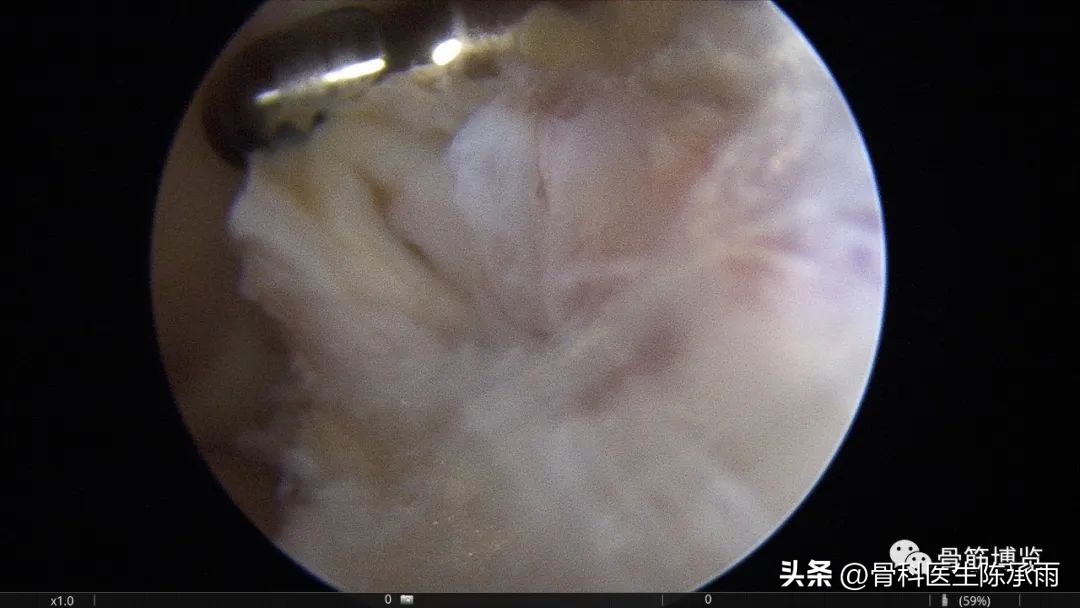

本例为内侧半月板前角巨大囊肿,关节镜下行半月板囊肿引流减压+囊肿前壁及囊壁滑膜切除+半月板缝合术。术中切除全部囊壁内滑膜及前壁及大部分后壁,保留部分后壁组织,以保证半月板前角缝合可靠及稳定。

术中情况